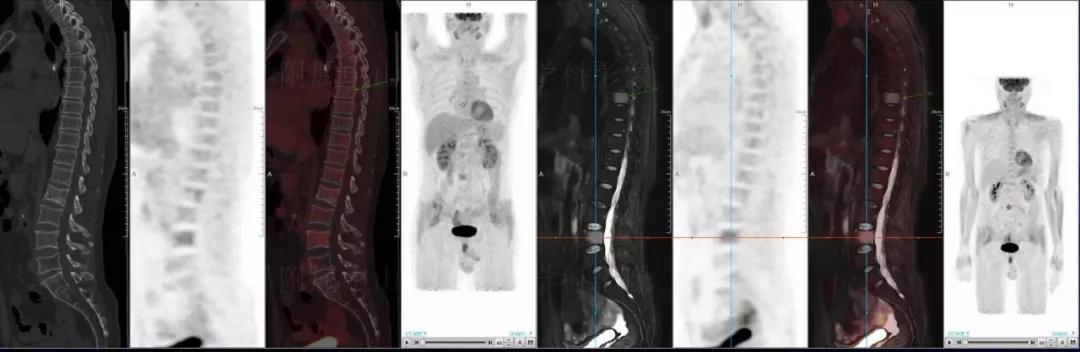

早在17年11月器械之家就曾報道過聯(lián)影“時、空一體”超清TOF PET/MR的問世。而現(xiàn)在,這臺國產(chǎn)首臺一體化PET/MR經(jīng)過1500多例臨床驗證,已獲國家藥品監(jiān)督管理局(CFDA)認(rèn)證,正式推向市場。

多發(fā)性骨髓瘤

中山醫(yī)院核醫(yī)學(xué)科基于聯(lián)影“時空一體”超清TOF PET/MR的融合顯像優(yōu)勢,進(jìn)行了大量的臨床掃描,發(fā)現(xiàn)多例由MGUS向多發(fā)性骨髓瘤轉(zhuǎn)變,并從中總結(jié)出了一定的共同征象,未來可能實現(xiàn)多發(fā)性骨髓瘤的早期篩查。此外,PET/MR在多發(fā)性骨髓瘤的療效評估方面,也存在顯著優(yōu)勢。

(男性,53歲。確診多發(fā)性骨髓瘤10月。經(jīng)過7周期VCD方案化療后,現(xiàn)行療效評價。)